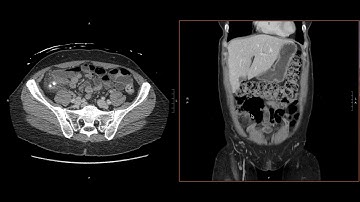

Abdominal Imaging Call Prep Cases: Acute Uncomplicated Appendicitis (CT) Case 3 Discussion